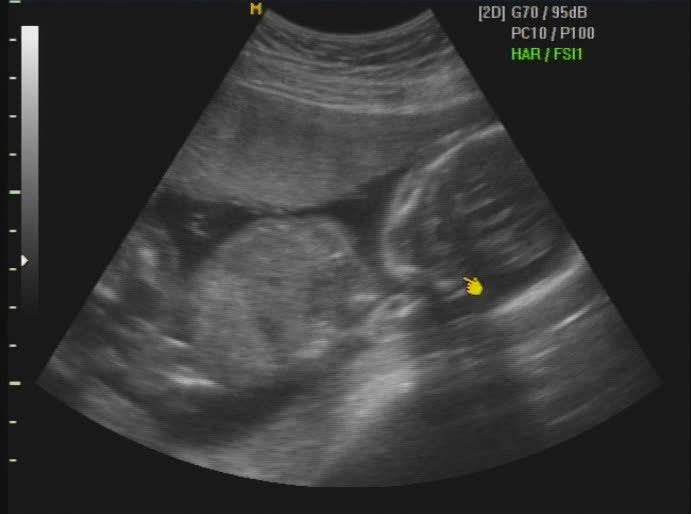

Hola a todos!, me presentaría, pero todavia no he nacido y no tengo nombre, se supone que lo haré aproximadamente el 26 de Marzo, mis papis (Dinís y Bárbara) acaban de enterarse de que voy a ser una niñita y están pensando en que nombre ponerme, a ellos les gustaría un nombre compuesto ya que es tradición en sus dos familias, pero como tienen un lio del carajo he decidido abrir este blog primero para que les ayudeis con mi nombre, y después para que sigais mi evolución como bebecita.